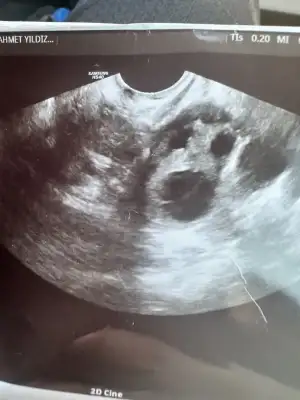

Merhaba kızlar bugün doktor muyanem vardı rahmime baltı yumurtan çatlamiş dedi döllenme var mı yok mu bir şey söylemdi rahmin kalınlaşmış dedi anlayan varsa bakabilir mi rica etsem 🥹